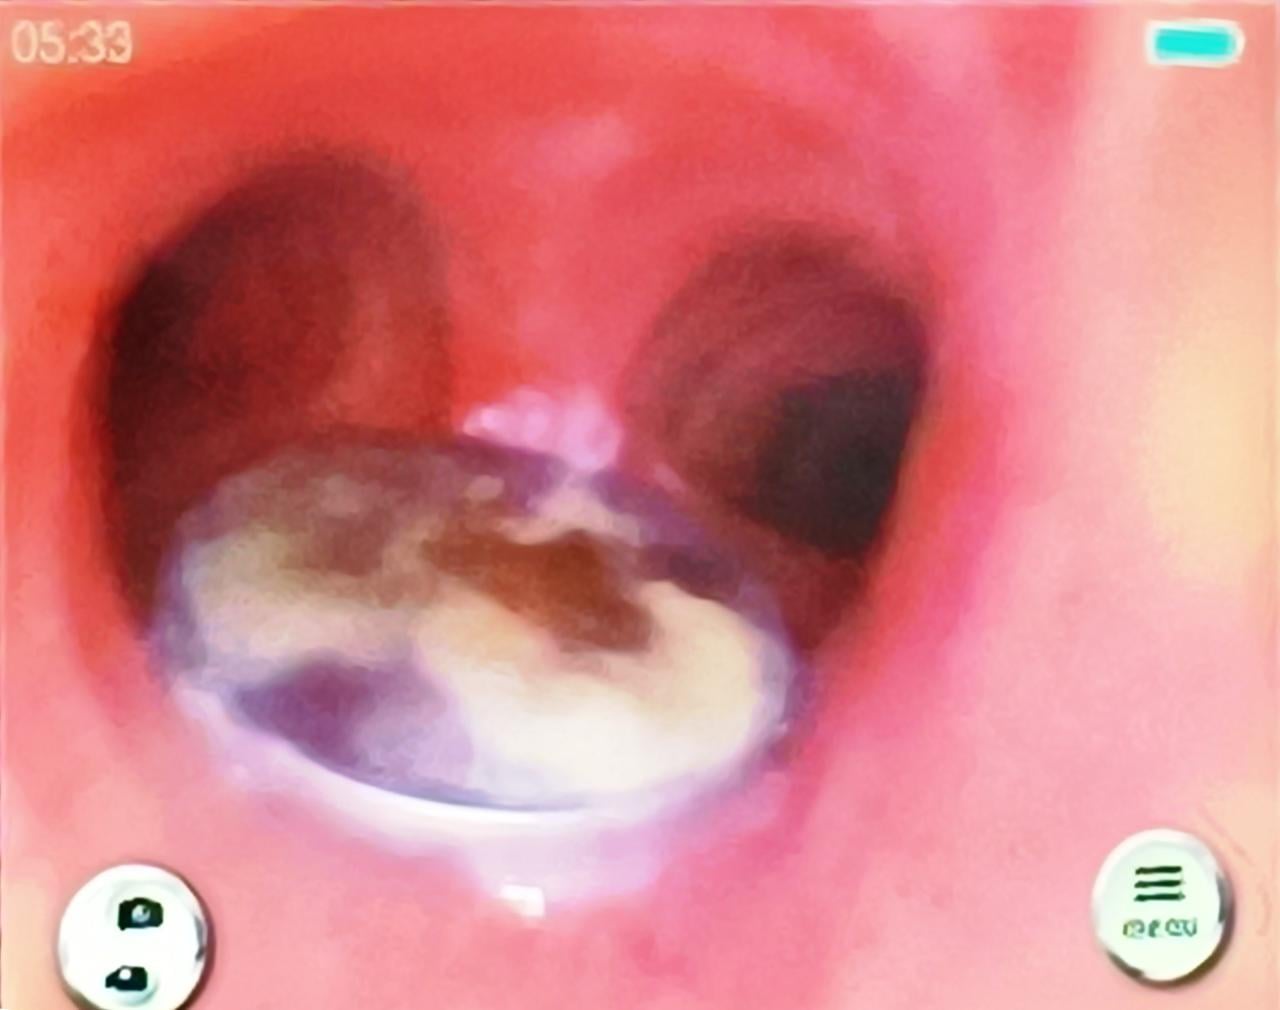

அவரை பரிசோதித்த வைத்தியர்கள், மூச்சுக்குழாயில் 25 சதம் நாணயக்குற்றி ஒன்று சிக்கி இருப்பதை கண்டுபிடித்தனர். இதையடுத்து  கடந்த 2ம் திகதி, கார்டியோ - தொராசிக் அறுவை சிகிச்சை மூலம், மூச்சுக்குழாயில் சிக்கியிருந்த நாணயத்தை வெற்றிகரமாக அகற்றியுள்ளனர்.

நாணயத்தை அகற்றிய பின்னர் அவர் நலமுடன் இருப்பதாக பனாரஸ் இந்து பல்கலைக்கழகத்தின் பேராசிரியர்கள் சித்தார்த் லகோடியா மற்றும் எஸ்.கே.மாத்தூர் ஆகியோர் தெரிவித்துள்ளனர்.